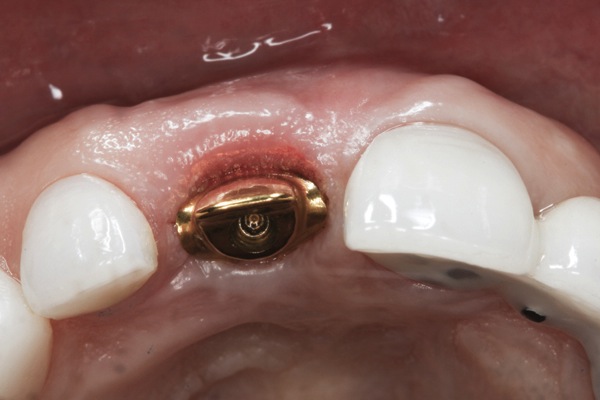

Fig 16. Try-in of the definitive titanium-nitride–coated abutment.

Figure 16

The implant impression, along with a cast of the opposing arch and shade, were sent to a commercial dental laboratory for fabrication of a master cast. A signed work order and the master cast were then sent to the BellaTek® Production Center (BIOMET 3i) for a lab-designed abutment (LDA) (Figure 14). A BellaTek® abutment was milled from a solid blank of titanium, and a gold-colored titanium-nitride coating was applied to impart a warm color through the thin marginal peri-implant tissues.

The master cast and abutment were returned to the laboratory for fabrication of the restoration (Figure 15). An all-ceramic crown (e.max®, Ivoclar Vivadent) was fabricated on the custom abutment; it matched the contours of the adjacent central incisor. After completion of custom shading, the definitive abutment and crown were returned to the restorative dentist. The abutment was tried in (Figure 16), and a radiograph was taken to confirm complete seating between the abutment/implant and the crown/abutment. The definitive abutment screw was torqued to 20 Ncm, and the screw-access opening was blocked out with Teflon tape.